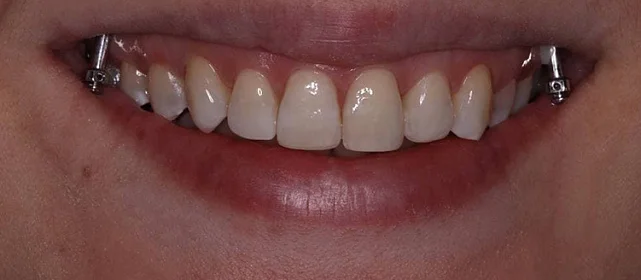

Проблема: Пациентка обратилась с одной жалобой — неровные зубы. При осмотре обнаружили, что обе челюсти сужены, зубам банально не хватает места, отсюда скученность. Зубы здоровые, ортопедия не нужна — чисто ортодонтический случай.

Решение: Установили брекеты на обе челюсти. Расширили дуги, убрали скученность — всё за 15 месяцев. Визиты раз в 4–6 недель для замены дуг. После снятия зафиксировали ретейнеры на обе челюсти, сняли сканы для кап. Ортопед подтвердил, что протезирование не требуется. Терапевт рекомендовал лечение — пациентка записана.

Пятнадцать месяцев!! Я морально готовилась к двум годам минимум, начиталась всякого в интернете. Виктория Юрьевна на первой консультации сказала, что случай не самый сложный и должны уложиться побыстрее. Так и вышло. Из неприятного — первая неделя после установки и пара дней после каждой замены дуги. В остальном нормально, привыкла быстро. Когда сняли и я увидела зубы — не поверила, что это мои. Теперь вот к терапевту надо сходить, подлечить пару зубов, и вообще всё.